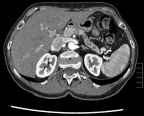

CHICAGO--(BUSINESS WIRE)-- Building on its advanced image reconstruction technologies, today Canon Medical Systems USA, Inc. introduces deep convolutional neural network (DCNN) image reconstruction, ushering in a new era for CT. Canon Medical’s Advanced Intelligent Clear-IQ Engine (AiCE) (pending 510(k) clearance) uses deep learning technology to differentiate signal from noise so that it can suppress noise while enhancing signal. The algorithm forges a new frontier for CT image reconstruction with its ability to learn from the high image quality of Model Based Iterative Reconstruction (MBIR) to reconstruct CT images with improved spatial resolution, 3-5x times faster than traditional MBIR.

Canon Medical Systems USA, Inc. introduces deep convolutional neural network (DCNN) image reconstruction, ushering in a new era for CT. (Graphic: Business Wire)

With AiCE’s deep learning approach, thousands of features learned during training help to differentiate signal from noise for improved resolution. AiCE applies a pre-trained DCNN to enhance spatial resolution while simultaneously reducing noise with reconstruction speeds fast enough for busy clinical environments.